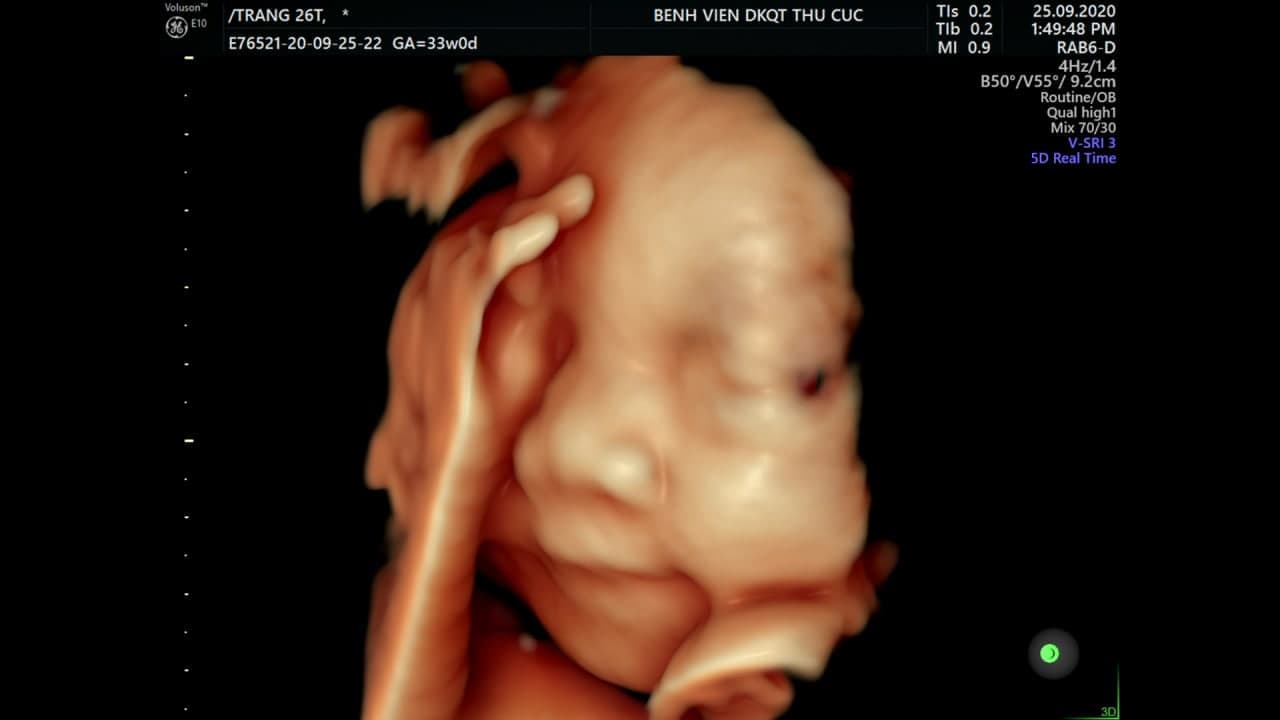

– Siêu âm 2D, 3D, 4D và 5D: Tổng hợp các tín hiệu để tạo dựng lên hình ảnh có các chiều tương ứng (2 chiều, 3 chiều, 4 chiều, 5 chiều).

Máy siêu âm 5D tại Hệ thống Y tế Thu Cúc TCI – Bước tiến vượt bậc trong lĩnh vực sản khoa, đem đến hình ảnh chân thực, sắc nét, giúp phát hiện sớm bất thường ở thai nhi